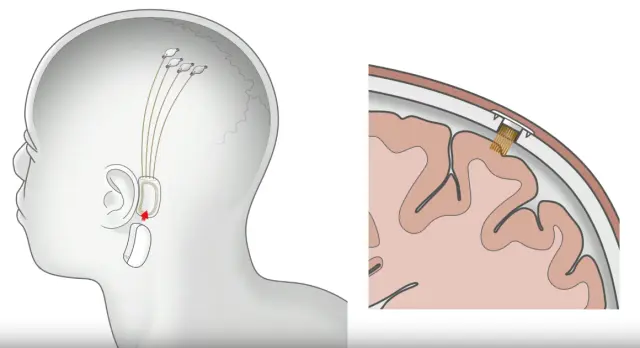

Uno de los avances más increíbles y que acapara todos los titulares en este campo es Neuralink, la empresa fundada por Elon Musk. La visión detrás de Neuralink es crear una interfaz cerebro-máquina que permita una comunicación directa entre el cerebro humano y los ordenadores.

Si bien esto suena a ciencia ficción, el proyecto ha avanzado mucho. Hace escasos meses, la startup tuvo la aprobación de la Administración de Alimentos y Medicamento de Estados Unidos (FDA), para su primer estudio clínico en humanos, y ya han conseguido la aprobación de una junta de revisión independiente para comenzar a reclutar pacientes para su primer ensayo en humanos.

Este primer ensayo se centrará en reclutar pacientes con parálisis, específicamente aquellos afectados por una lesión de la médula espinal cervical o esclerosis lateral amiotrófica (ELA).